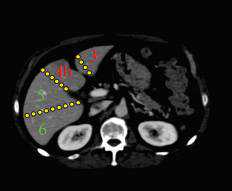

CT轴位分段

肝左右叶(IV段与V、VIII段)分界:沿胆囊窝上方肝中静脉至下腔静脉(下图红线)。

肝左叶(内侧II、III段与外侧IV段)分界:沿镰状韧带和肝左静脉、肝中静脉汇合处下腔静脉连线(下图蓝线)。

肝右叶(前侧V/VIII段与后侧VI/VII段)分界:沿下腔静脉下方肝右静脉至肝脏边缘(下图绿线)。

尾状叶:尾状叶(I段)在后方,尾状叶与其他叶不同的是,它经常经静脉直接与下腔静脉,而不通过肝静脉主干,也有可能同时接受门静脉左右支的血供。(下图C)

简单记忆方法:

上:7842

下:6543